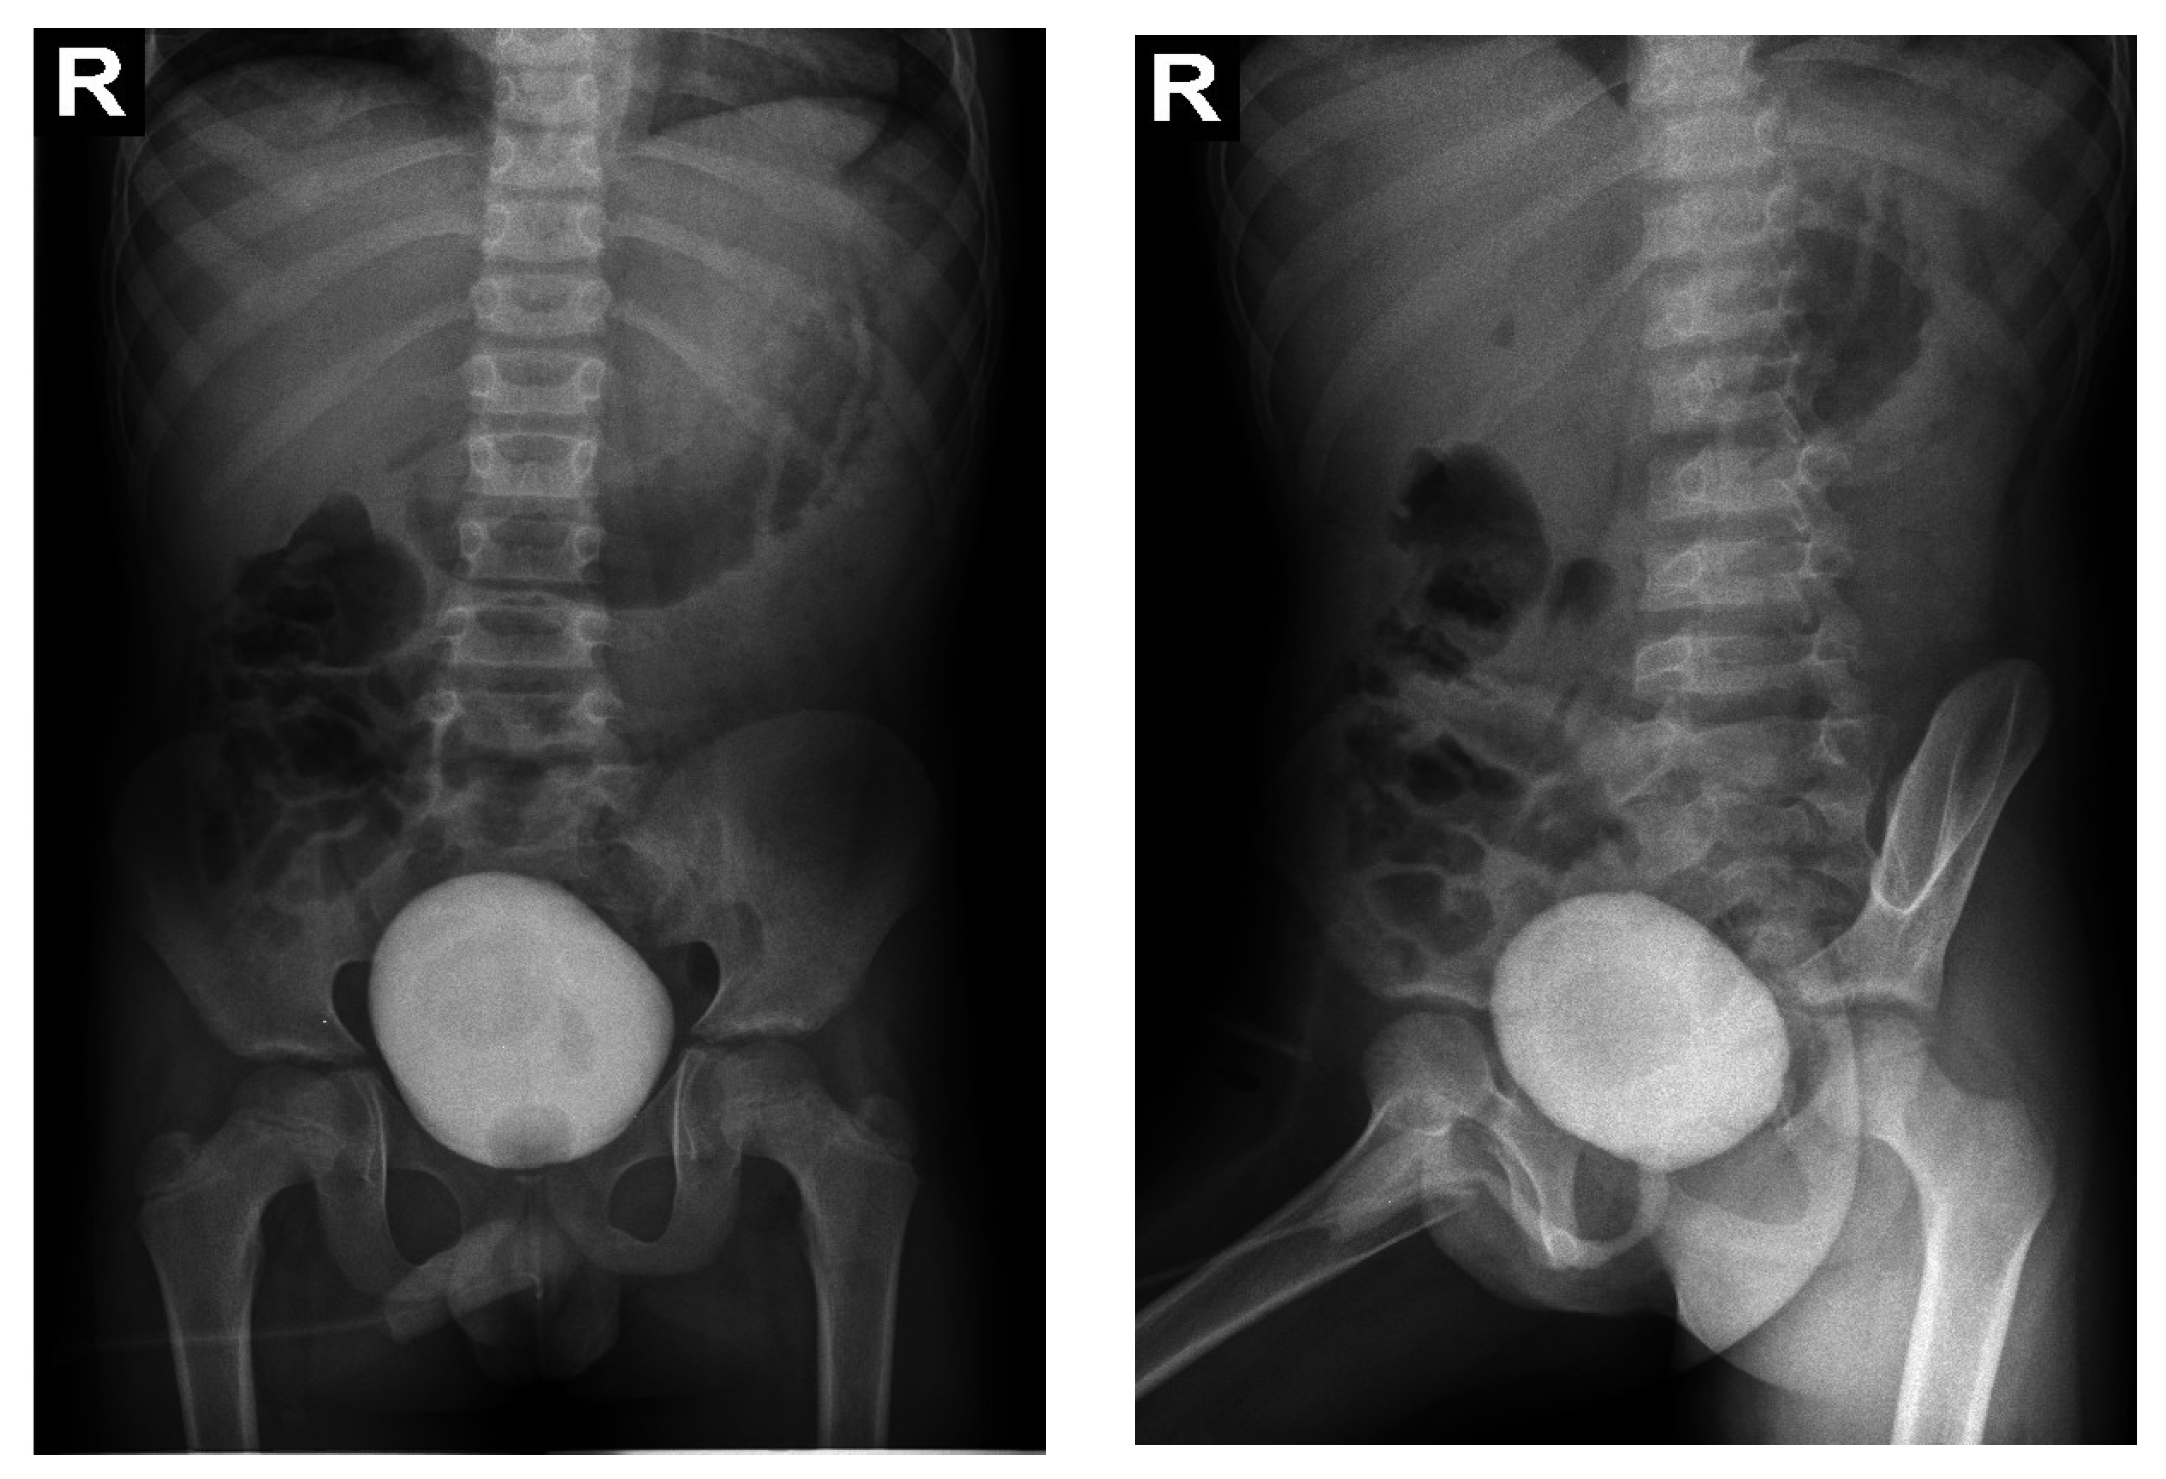

Enzyme replacement therapy (ERT) (Agalsidase β) was subsequently initiated, under which the patient showed a favorable evolution, with the disappearance of palmo-plantar burning acroparesthesias after 3 months of therapy, the normalization of the echocardiographic appearance and the disappearance of left ventricular hypertrophy after 6 months and the disappearance of renal hyperechoic formations on CT-scan after 12 months (Figure 13). Enzyme activity was also tested on the mother and the sister, the mother showing α-galactosidase deficiency.

Figure 13. Abdominal CT scan—disappearance of renal hyperechoic formations (blue arrow).